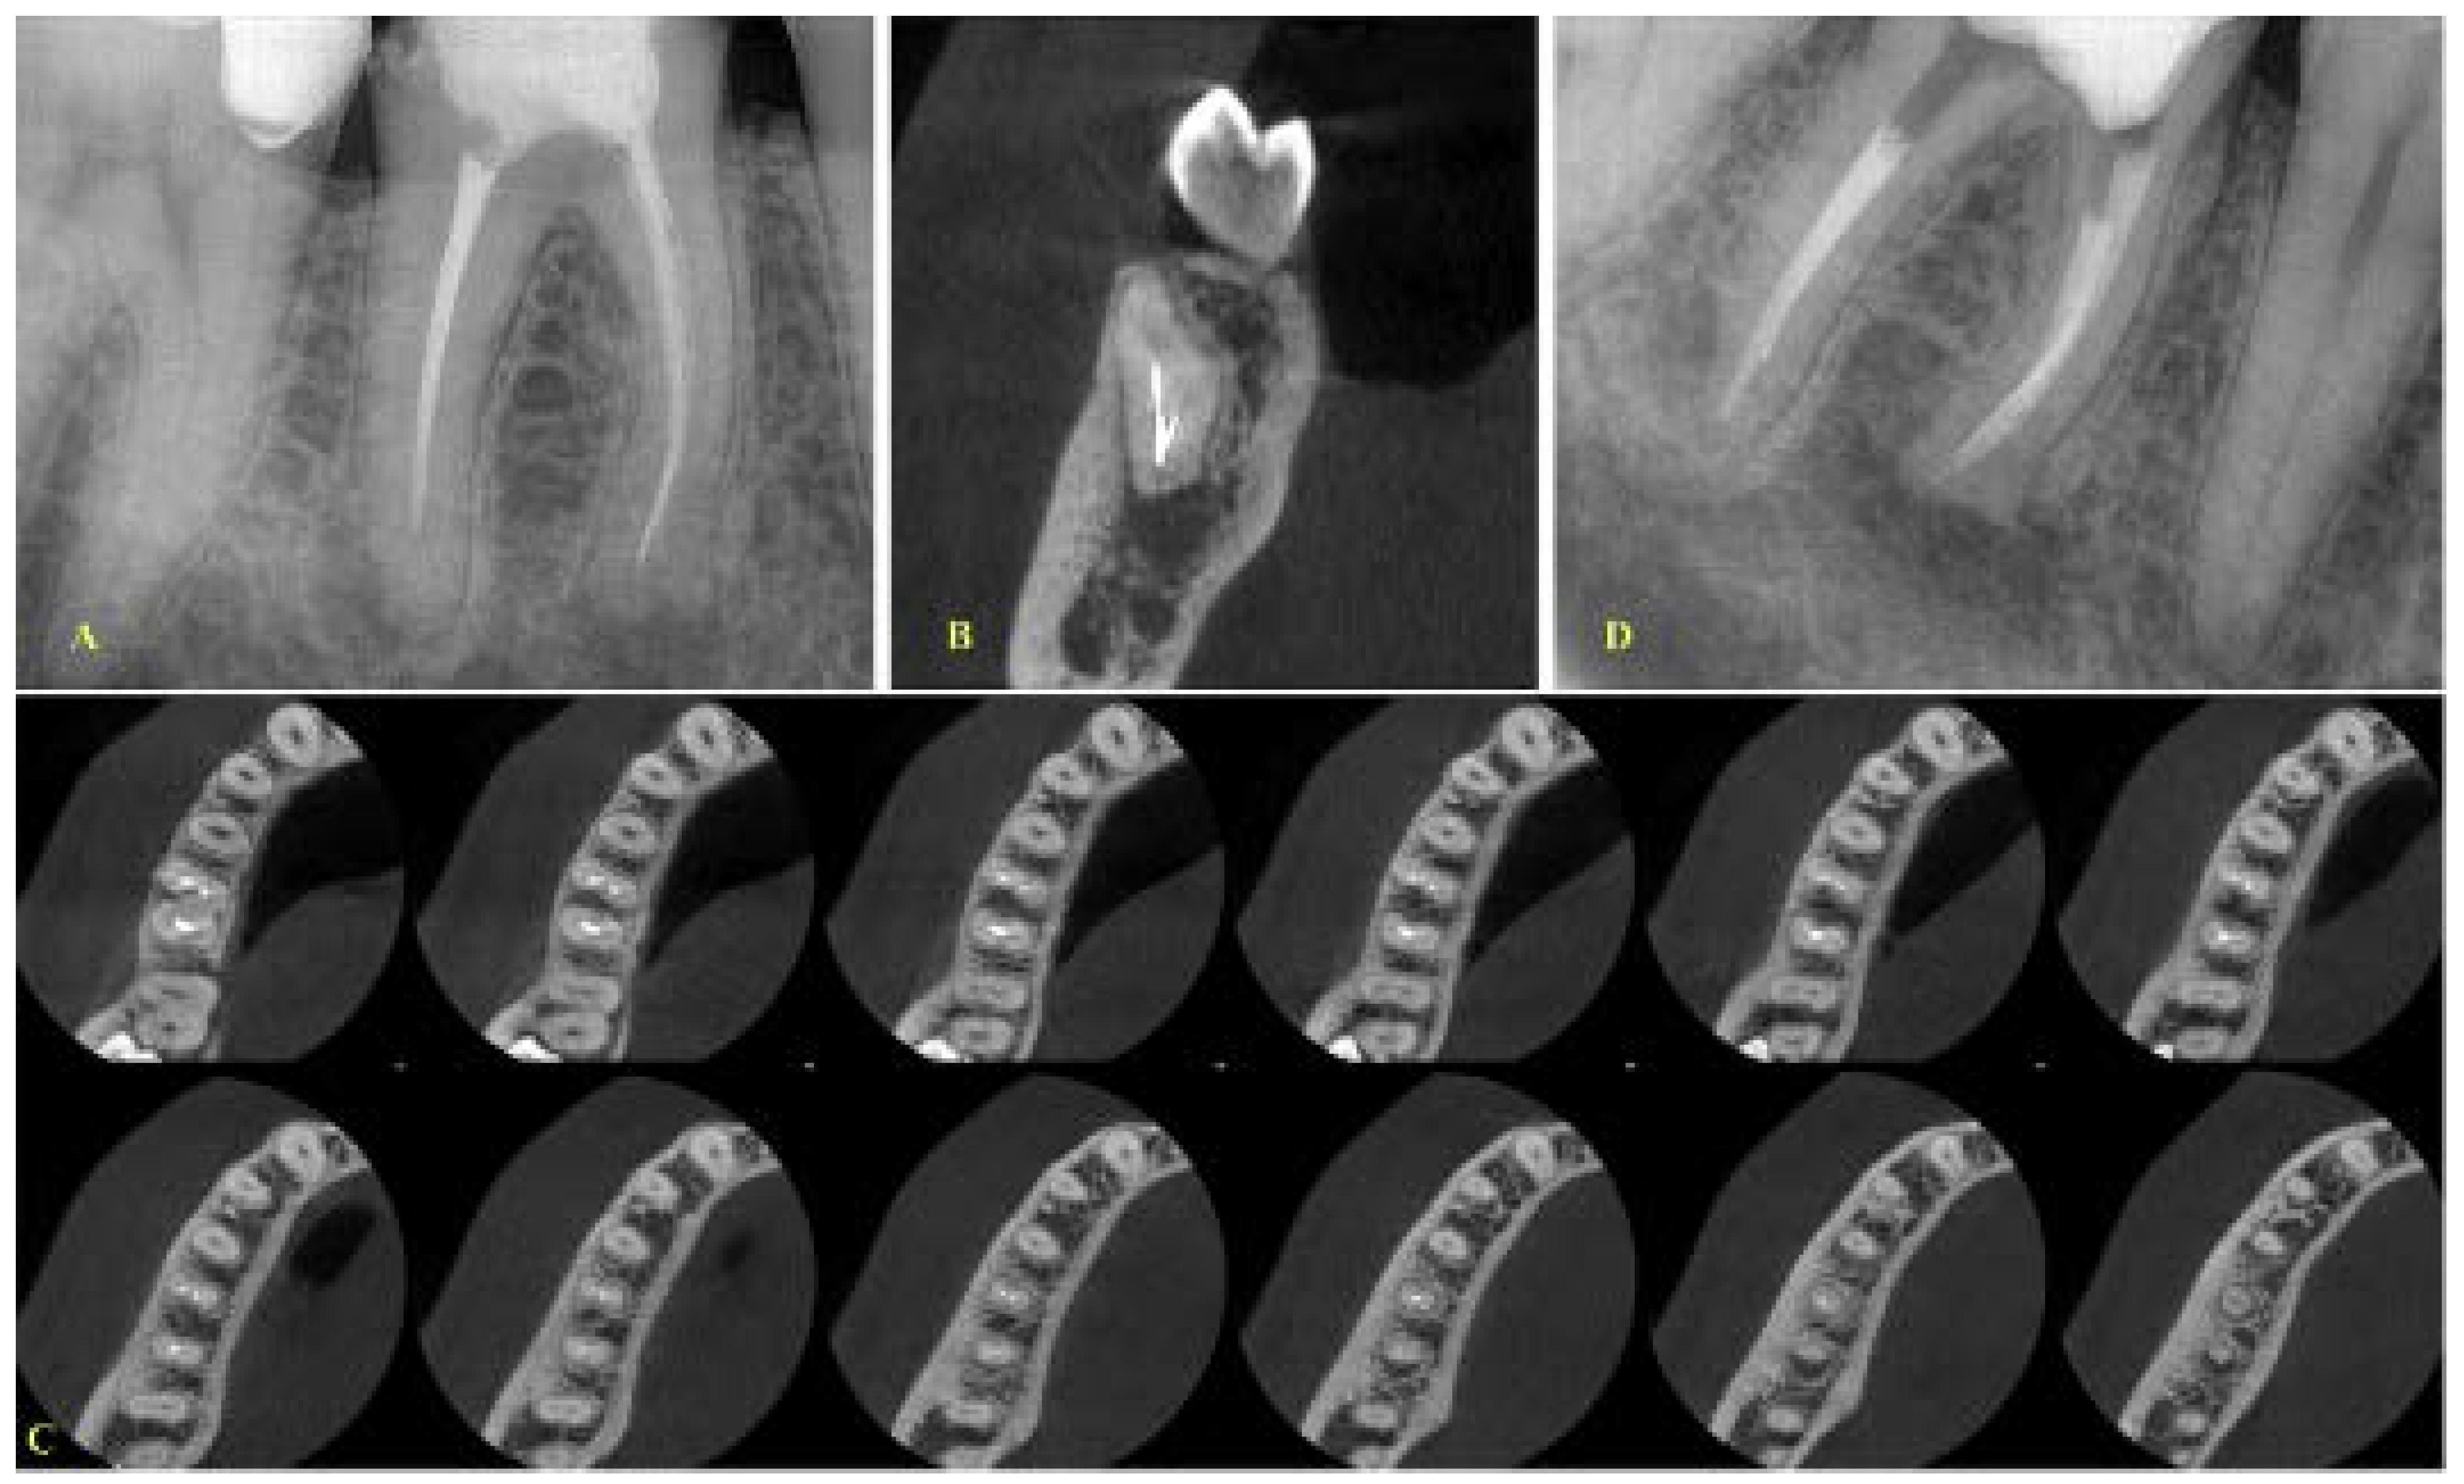

- If the fragment was located at the middle level, the canals were separate and the curvature was not severe as indicated after evaluation of the coronal CBCT images; then, a removal attempt was made, especially in cases where the length of the fragment was short (Figure 2).